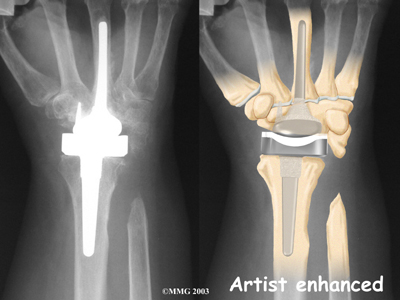

The wrist joint is replaced with an artificial joint (also called a prosthesis) much less often than other joints in the body, such as the knee or the hip. Still, when necessary, this operation can effectively relieve the pain caused by wrist arthritis. When severe arthritis has destroyed the wrist joint, artificial wrist replacement surgery (also called wrist arthroplasty) can help restore wrist strength and motion for many patients.

- what parts of the wrist are replaced